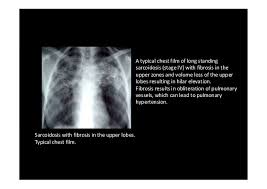

Interstitial lung disease results in six distinct radiologic patterns of abnormality. Interstitial lung disease ILD drug-induced interstitial lung disease. We describe demographic radiologic histopathologic and molecular features and p16 expression in patients with telomeres 10th percentile shortened telomeres and compare them to patients with telomere length 10th percentile.

Morphologic classifications of lung conditions diffuse interstitial lung diseases in particular have been undertaken both at the microscopic pathologic patterns and gross radiographic or thin-section computed tomographic CT patterns level. Reticular nodular high and low attenuation table. The lung interstitium is the space where the air sacs called alveoli come in contact with connective tissue and blood vessels to exchange oxygen and carbon dioxide.

Radiographic evidence of interstitial fibrosis consisting of a reticular pattern that involves mainly the lower lung zones is seen in only about 3 of patients who have systemic lupus erythematosus. Interstitial lung disease ILD in pediatric patients is different from that in adults with a vast array of pathologic conditions unique to childhood varied modes of presentation and a different range of radiologic appearances. By contrast interstitial abnormalities are seen in approximately 30 of patients at high-resolution CT 21 22.